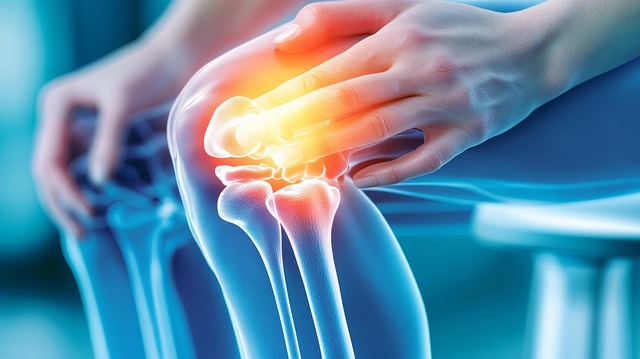

고관절은 걷기, 뛰기, 앉기 등 거의 모든 움직임에 관여하며 체중을 직접 지탱합니다. 연골 손상, 근육 불균형, 점액낭 염증, 과사용 등이 주요 원인입니다. 고관절 내부는 연골·관절막·Labrum·근육·힘줄이 밀집되어 있어, 어디가 문제인지에 따라 고관절 통증 증상이 달라집니다. 사타구니 당김은 내부 구조 문제, 옆쪽 통증은 점액낭 문제, 찝힘은 충돌증후군과 관련 있을 가능성이 높습니다.

2. 대표 고관절 통증 증상 8가지

아래 증상 중 2개 이상 해당한다면 조기 관리가 필요합니다.